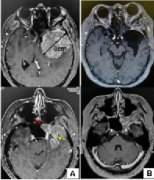

然而随着显微技术领域取得的较大进展,同Cushing和其他先前外科医生的探索性努力相比,显微外科技术能在较低的病残率和死亡率的基础上全切那些肿瘤。因为根治性切除蝶骨嵴内侧脑膜...

蝶骨嵴脑膜瘤严重吗?下文报告了一例患者,其中蝶窦蝶骨嵴脑膜瘤是通过分期手术切除的,包括颅内部分的开颅手术和蝶窦颅外部分经蝶和经蝶入路的内窥镜鼻内切除术。接下来,打开左侧鼻...